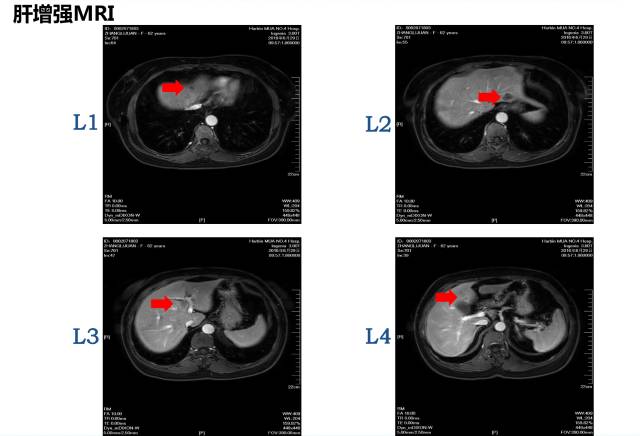

病理:盲肠腺癌肝脏MRI:共8枚病灶

1 2 肝转移病灶

邢宝才教授:1cm以上的病灶影像学特征较为明显,1cm以下的不明显病灶可以进行超声造影,CT敏感性约为80%,核磁共振(MRI)敏感性约90%多,核磁共振(MRI)+ 普美显敏感性约96~97%。针对小病灶,核磁+普美显的肝胆特异期联合DWI的检测误差较小。术前我们对病灶应进行细致的影像学评估,而判断是否转移应以术后病理结果为准。